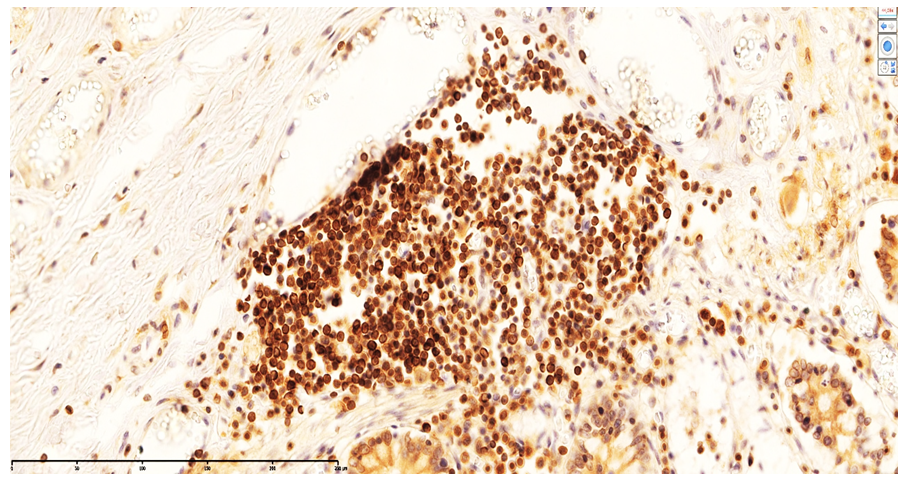

These findings indicate that monocytes and macrophages bearing the CD4 antigen—cells participating in T-lymphocytic immunity—are located in the lamina propria of the ileal mucosa and in the submucosa.In neonates who died on days 20–22 of NEC, the appearance of T lymphocytes in the lamina propria of the ileal mucosa was confirmed by low positive CD3 expression. These cells accumulated around postcapillary venules in the lamina propria, forming T-cell areas. At the same time, CD4-positive monocytes and macrophages were sparsely and diffusely expressed in other regions of the lamina propria. Because all layers of the ileal wall are diffusely affected in NEC, sparse CD4-positive monocytic/macrophagal cells and CD3-positive T lymphocytes were observed in the interstitial tissue across all layers, with weak reactions in some sites.Overall, examination of CD3+ and CD4+ markers showed low positive expression in MALT during NEC; values for the 0–7-day and 8–28-day periods were close to each other. The paucity of CD3+CD4+ T helpers indicates immunodeficiency and a marked reduction in resistance to infection. Based on these data, the process continues throughout days 0–28; in our study, nosocomial infection and the degree of intestinal injury were highest during days 8–28 of NEC.Ki-67 marker. Ki-67 is expressed in the perinuclear region of many cell types and serves as a marker of proliferative activity, playing an important role in evaluating the proliferation index of T lymphocytes. In immunohistochemistry, Ki-67 is expressed to varying degrees (light, moderate, strong brown) throughout all active phases of the cell cycle (G1, S, G2, M), with highest expression from early G1 to M and clear visualization at metaphase. In early G1, Ki-67 localizes to centromeric satellite DNA and telomeres; in mid-cycle phases it is detected intranuclearly within the nucleolus; by G2 it is expressed in the nucleolus and karyoplasm. After mitosis, as the cell enters G0, Ki-67 undergoes proteasomal degradation and is not expressed during interphase. In our work, this is critical for marking the proliferative phase during the formation of lymphocytes in MALT.Using Ki-67, a proliferation index can be calculated. With the modern QuPath-0.5.0 platform, automated commands allow counting of positively expressing nuclei at 200× and 400× magnification with 98.5% accuracy, minimizing human bias; the percentage of positively expressing cells is then computed.Grading by positive fraction:<10% — low;10–20% — moderate;>20% — high expression. | Figure 4. Strong CD20 expression in B lymphocytes within MALT of a neonate who died on day 22 of NEC. DAB chromogen. 10×40 |

B-cell activity (CD20). Immunohistochemistry showed that, in the early stages of NEC in the ileum, B lymphocytes in interfollicular areas become activated; intrafollicular CD20 expression indicates B-cell proliferation. | Figure 5. Low-level CD20 expression in the lamina propria of the ileal mucosa. DAB chromogen. 10×40 |

Variability in the size of CD20-positive lymphocytes indicates the presence of B lymphocytes, lymphocytic immunoblasts, and plasma cells. In the intestinal form of neonatal sepsis, the near absence of lymphoid follicles in the ileum reflects immaturity. Accordingly, CD20 expression is generally low and appears as small, scattered B-cell clusters across the mucosa. Our study showed that, because MALT structures are not fully developed in NEC-affected ileum, CD20 strongly expressed in small clusters represents primary follicles that have not yet transformed into secondary follicles. | Figure 6. Small-cluster CD20 expression in primary lymphoid follicles of the ileal mucosa. DAB chromogen. Magnification ×400 |

In the development of a systemic vascular response in NEC, a desquamative ulcerative ileitis forms in the ileal mucosa: the covering epithelium sloughs off and ulcers appear in the lamina propria. At the base of the ulcers, cellular infiltrates from MALT persist alongside connective tissue of the lamina propria. Within MALT, CD3-positive T lymphocytes show very low expression; they are densely arranged, variable in size, and interwoven with connective tissue cells. In neonates who died within 0–7 days, the MALT layer consisted only of primary lymphoid follicles. Thus, in newborns, T-cellular immunity is not fully developed; T-cell areas do not form in peripheral MALT, and T cells do not participate in the infectious process in NEC. Immunohistochemical processing of ileal sections revealed weak CD3 expression.On days 7–8 of NEC, very strong and dense CD20 expression was detected in lymphocytes within ileal lymphoid follicles. This suggests that infection-induced somatic hypermutation occurred in B lymphocytes, leading to the formation of numerous high-affinity receptors and the emergence of long-lived plasma cells; strong CD20 expression and the presence of larger, more elongated plasma cells were noted. These effector cells synthesize immunoglobulins IgM/IgD/IgG [7]. Despite infection, CD3 and CD4 (T-cell markers) showed low expression in the mucosa and submucosa during the systemic response in the ileum. Thus, cellular immunity markers were expressed sparsely and at low levels, paralleling the B-cell (humoral) response.

Immunohistochemical studies show that, in NEC during the 0–7-day period, B lymphocytes are activated within primary lymphoid follicles of the ileal wall; initial intrafollicular CD20 expression indicates B-cell proliferation.